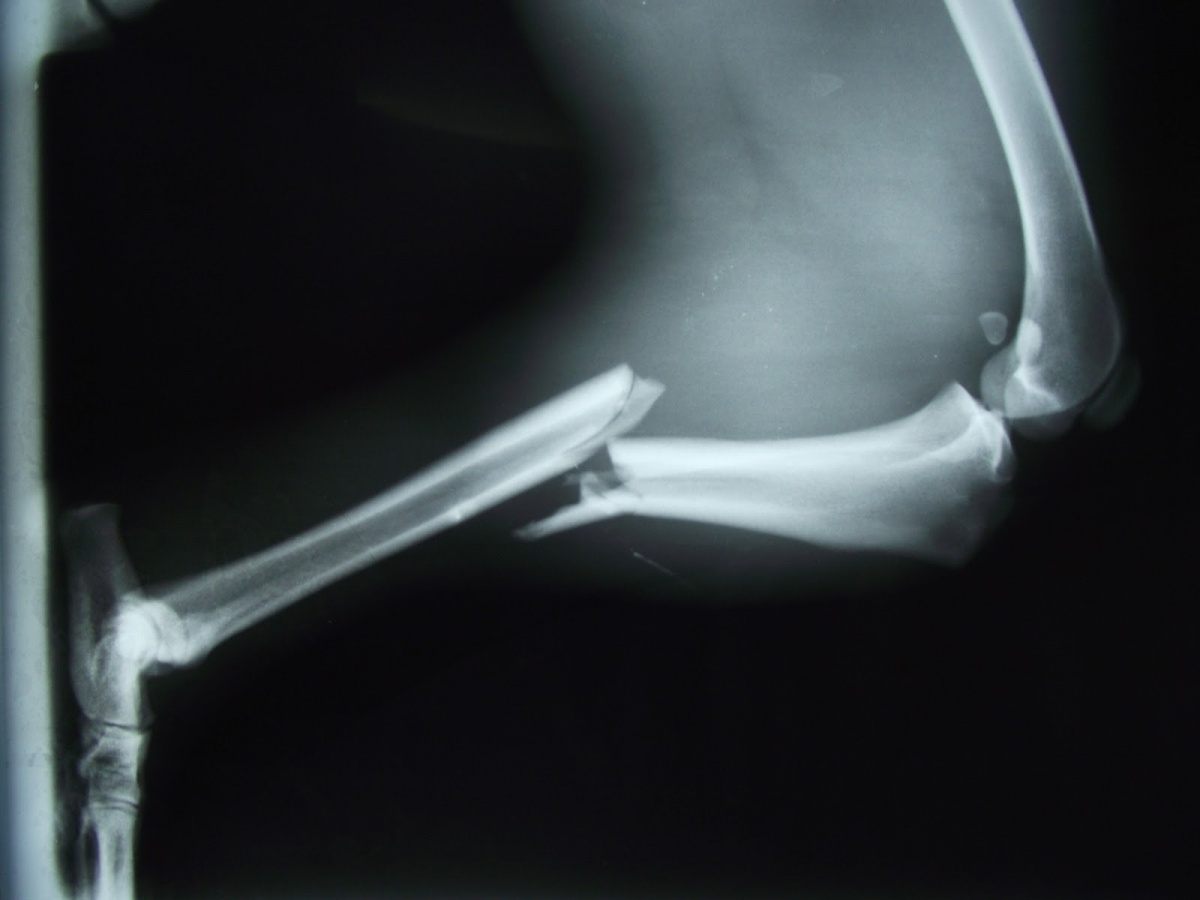

Vastag gipsz helyett 3D-s technológiával rögzíthetik a töréseket egy magyar informatikus ötletének köszönhetően, aki finanszírozót keres a megvalósításhoz – írta csütörtökön a Népszabadság.

Molnár Miklós a napilap cikke szerint egy szoftver segítségével 12 óra alatt nyomtatta kis a csuklójára megfelelő szorítót. A projektben az új rögzítés tesztelésére a fővárosi baleseti központ mellett a kecskeméti megyei kórház és a szegedi egyetem traumatológiája is részt venne. A programhoz az uniós kutatás-fejlesztési pályázaton szeretnének pénzt nyerni.

Az előzetes számítások szerint egy kisebb 3D-s csuklórögzítő ára 10 ezer, egy nagyobb, bokarögzítő 15-20 ezer forintba kerülhet. Tóth Ferenc, a Péterfy Sándor utcai Kórház rendelőintézet és Baleseti Központ igazgatóhelyettes főorvosa, aki Molnár Miklóssal együtt dolgozik a projekten a Népszabadságnak azt mondta, a végtagszkennelés után néhány óra alatt elkészíthető az eszköz, amelyet akár hónapokig is lehet viselni. Súlya mindössze 50 gramm, de masszívabb és tartósabb, mint a most használt gipsz.